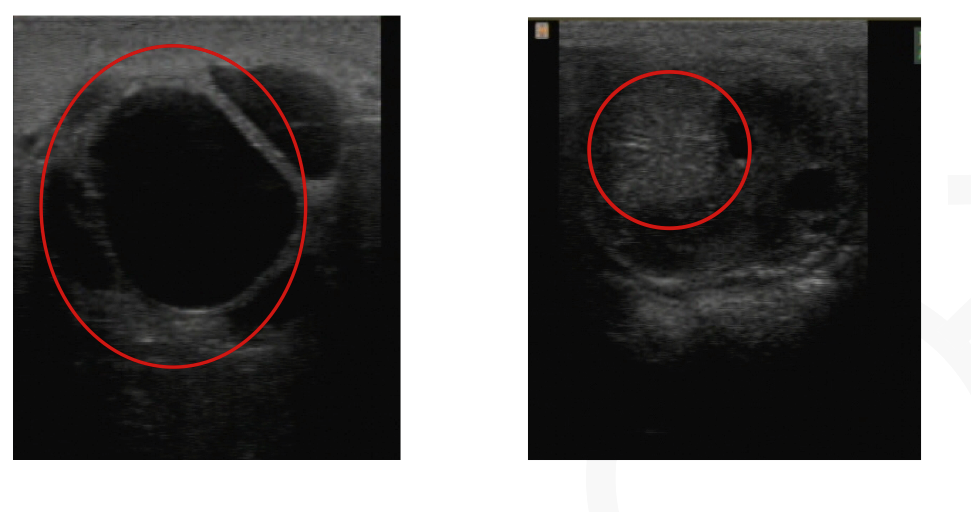

Retained testicle

What are the four possible anatomical locations for the retained testicle?